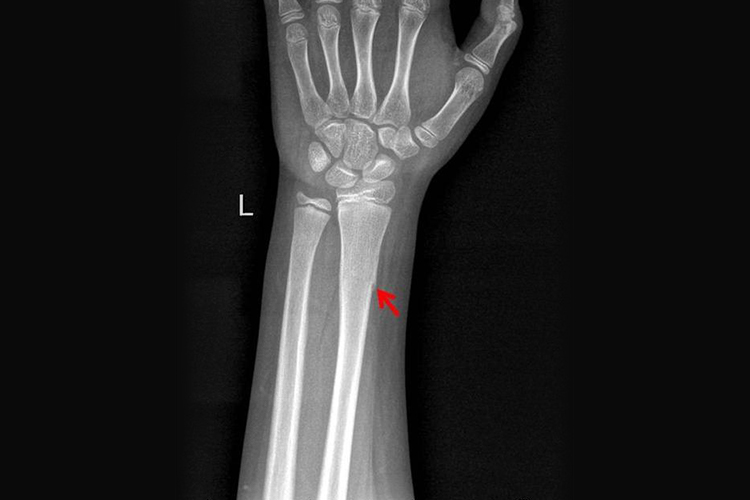

- 原始骨痂形成期:在骨折后的2周左右,骨折端之间开始有骨组织进行连接,形成原始骨痂,可能持续数周至数月。